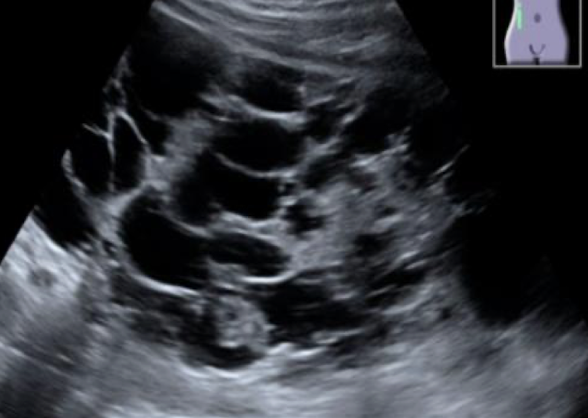

?? describe

autosomal dominant polycystic kidney

“multiple cystic structures noted throughout RK. ?polycystic kidney dz”

??

autosomal dominant polycystic kidney (ADPKD)